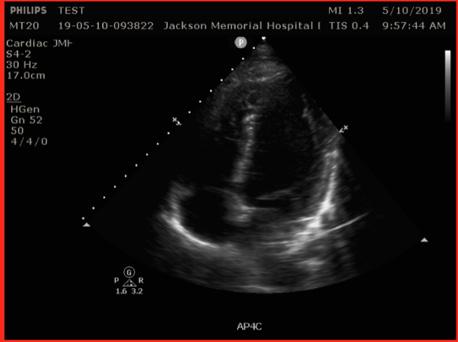

TECHNIQUE A. Cardiac

Probe: Phased array probe

D-Sign 22% 26% 64% 97% 95% 61% Pre-set: Cardiac Patient position: Supine position with left arm over the head; left lateral decubitus may help bring the heart closer to the chest wall in order to achieve a better apical four-chamber (AP4C) view. Technique: If the display marker is on the left, the probe marker will point to the left hip for the parasternal long axis view (PSLAX), the right hip for the parasternal short axis view (PSSAX), and the right flank for the sub-xiphoid (SX) and AP4C.

POCUS SIGNS A. Cardiac

Based on a meta-analysis published by Fields et al. in 2017, undefined right heart strain is a common ultrasound finding in PE with a sensitivity of 53% (95% CI, 45%-61%) and a specificity of 83% (95% CI, 74%-90%). Multiple other ultrasonographic signs, including ventricle size ratio, paradoxical septal motion, tricuspid regurgitation, 60/60 sign, McConnell’s sign, right heart thrombus, right ventricle (RV) hypokinesis, pulmonary hypertension, RV end-diastolic diameter, tricuspid annular plane systolic excursion, RV systolic pressure, and early systolic notching, have been identified. Due to variable specificities and sensitivities (Fig. 1), no single sign is sufficient to exclude PE. Although, degrees of knee flexion.

the most specific sign. The following six signs (three related to size and three related to function) are simple to perform and suggest acute right heart strain.

Size: (1) RV dilatation, (2) McConnell’s sign, and (3) D-Sign Function: (4) TAPSE, (5) S’, and (6) FAC

1. Right Ventricular Dilatation

Significance: RV dilatation is suggestive of acute RV strain. Technique: RV end diastolic diameter should be measured at the midlevel in the AP4C view. A diameter greater than 35mm is suggestive of RV dilatation. Alternatively, obtaining a ratio of RV to LV enddiastolic diameter greater than 0.6 is considered abnormal.

2. McConnell’s Sign

Significance: McConnell et al. compared RV dysfunction in patients with acute PE with patients with chronic pulmonary hypertension, and found that the cardiac echocardiogram in patients with acute RV strain had an akinetic RV free wall while the apex had normal contractions. McConnell’s sign is 94% sensitive for acute right heart strain. In subsequent studies, this sign has been found in patients with acute RV infarct and 17% of chronic pulmonary hypertension,

and thus is far from definitive proof of PE. Technique: McConnell’s sign is visualized best in the AP4C view.

4. Tricuspid Annular Plane Systolic Excursion (TAPSE) (Fig. 2)

Significance: RV function has been shown to correlate with the RV free wall excursion, or TAPSE. Preliminary studies also suggest that the use of TAPSE in tachycardic and hypotensive patients increases the sensitivity for identifying acute PE. A normal value is >20 mm, and excursion of less than 16mm is considered abnormal, and suggestive of RV systolic dysfunction and, consequently, RV strain. Technique: The goal is to measure the movement of the tricuspid annulus from the end of diastole to the end of systole using M-mode. Step 1: Obtain the A4C view. Step 2: Place the M-mode marker through the lateral tricuspid annulus. Step 3: Measure the distance from the peak to the valley.